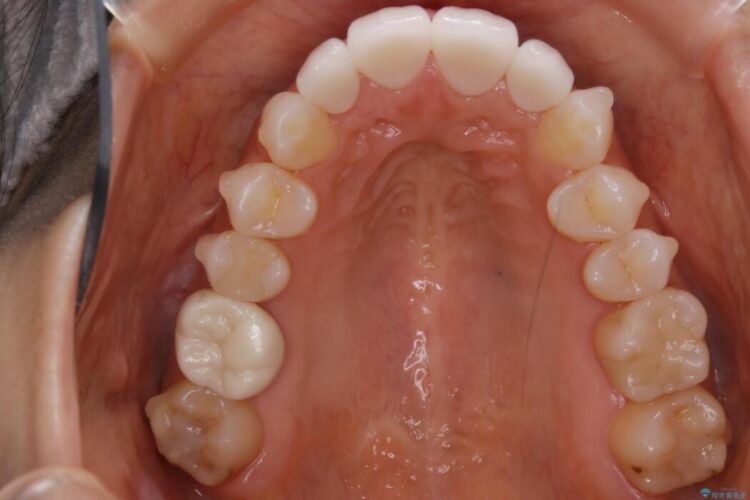

軽度のガタつきと不正咬合が見受けられましたので、インビザラインでの矯正治療を計画しました。

また確認したところ前歯と奥歯にセラミッククラウンで治療した歯があったため、そちらに影響のない範囲内で口腔内全体の噛み合わせが改善されるように歯を動かしていくことになりました。

既定のインビザラインの装着時間を守っていただけたこともあり整ったアーチとなりました。

本症例ではセラミッククラウンのかぶせ物をした歯が複数ありました。

セラミック等の被せ物がある場合、それ自体の外形は矯正治療では変えられないため天然歯の移動に影響を与えてしまうことがあります。

加えてインビザラインでの治療上設定されるアタッチメント(歯の表面に付けるプラスチックの突起)が外れやすい場合が多く、歯の移動に対する力が不足する可能性があります。